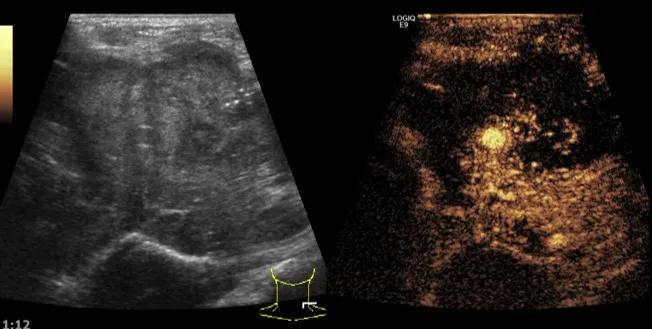

第5例是乳腺癌的患者,右乳恶性肿瘤术后化疗后1年出现淋巴结转移,患者基本情况差,拒绝放化疗,行局部热消融后也实现充盈缺损,术后一个月强化信号消失。

(病例5图例)